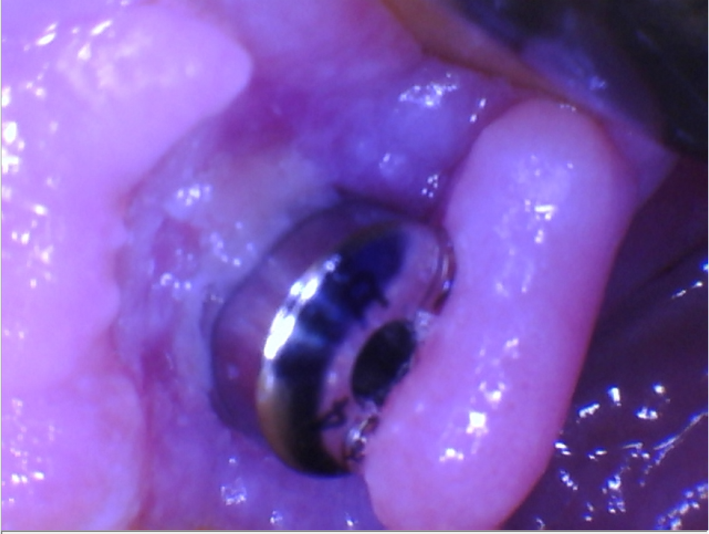

2nd/3rd picture – Week 3 post op

At the post op visit, noticed some purulence around the healing abutment along with the buccal tissue being flappy without any kind of closure. Also took a PA and noticed a distinct RL around the implant. Shit sucked.

Thinking about the case, maybe one of sutures unwinded and left that buccal tissue unattached, causing bacteria to settle in? Or maybe I should’ve just placed the cover screw and not trying to rush things. Who knows.